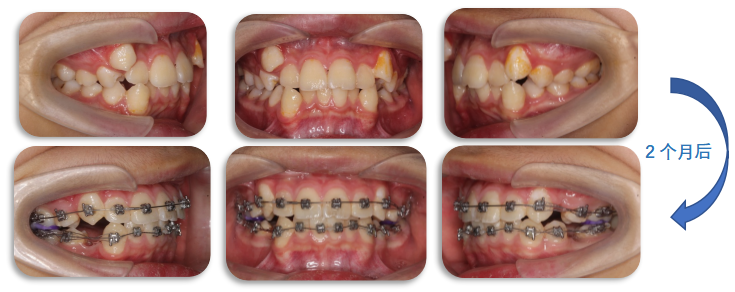

治疗前

拔牙治疗中

矫治前

拔牙矫治中

颏部形态逐渐显现,面型改善明显